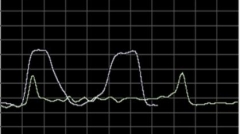

中医正骨多源信息采集系统成果简介

发布:中医药创新转化研究院